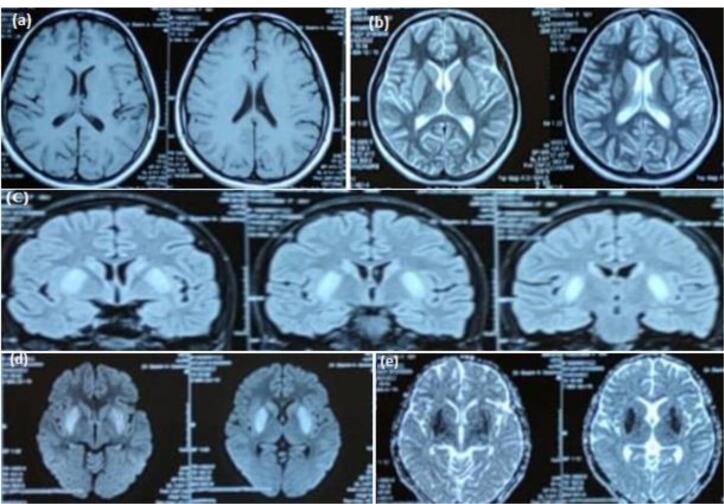

eb病毒(EBV)与传染性单核细胞增多症有关,虽然很少,但已知会引起各种神经系统并发症。EBV脑炎是一种罕见的表现,更罕见的是其表现为癫痫持续状态。迄今为止,全球报告的以癫痫持续状态表现的EBV脑炎病例不足10例。我们报告一例18岁的女孩谁提出发烧,随后癫痫发作。第二天她进入了癫痫持续状态。脑脊液(CSF)分析显示淋巴细胞优势。脑成像显示双侧对称的尾状核和壳核高强度病变。EBV IgG和IgM阳性。患者给予更昔洛韦和抗癫痫药物治疗,病情逐渐好转。我们的病例强调了考虑EBV脑炎作为癫痫持续状态的潜在原因的重要性,即使在没有免疫缺陷的个体中也是如此。认识到非典型的表现和适当的诊断调查可以促进早期诊断和治疗的开始。

Epstein-Barr virus (EBV) is associated with infectious mononucleosis and is known to cause various neurological complications, albeit rarely. EBV encephalitis is a rare manifestation, and even rarer is its presentation as status epilepticus. To date, fewer than ten cases of EBV encephalitis presenting as status epilepticus have been reported globally. We report a case of an 18-year-old girl who presented with fever followed by seizures. She went into status epilepticus the next day. Cerebrospinal fluid (CSF) analysis showed lymphocytic predominance. Brain imaging showed bilateral symmetric hyperintense lesions in the caudate and the putamen. EBV IgG and IgM were found to be positive. The patient was treated with ganciclovir and anti-epileptics and she improved gradually. Our case emphasizes the importance of considering EBV encephalitis as a potential cause of status epilepticus, even in individuals without immunodeficiency. Recognizing atypical presentations and appropriate diagnostic investigations can facilitate early diagnosis and treatment initiation.